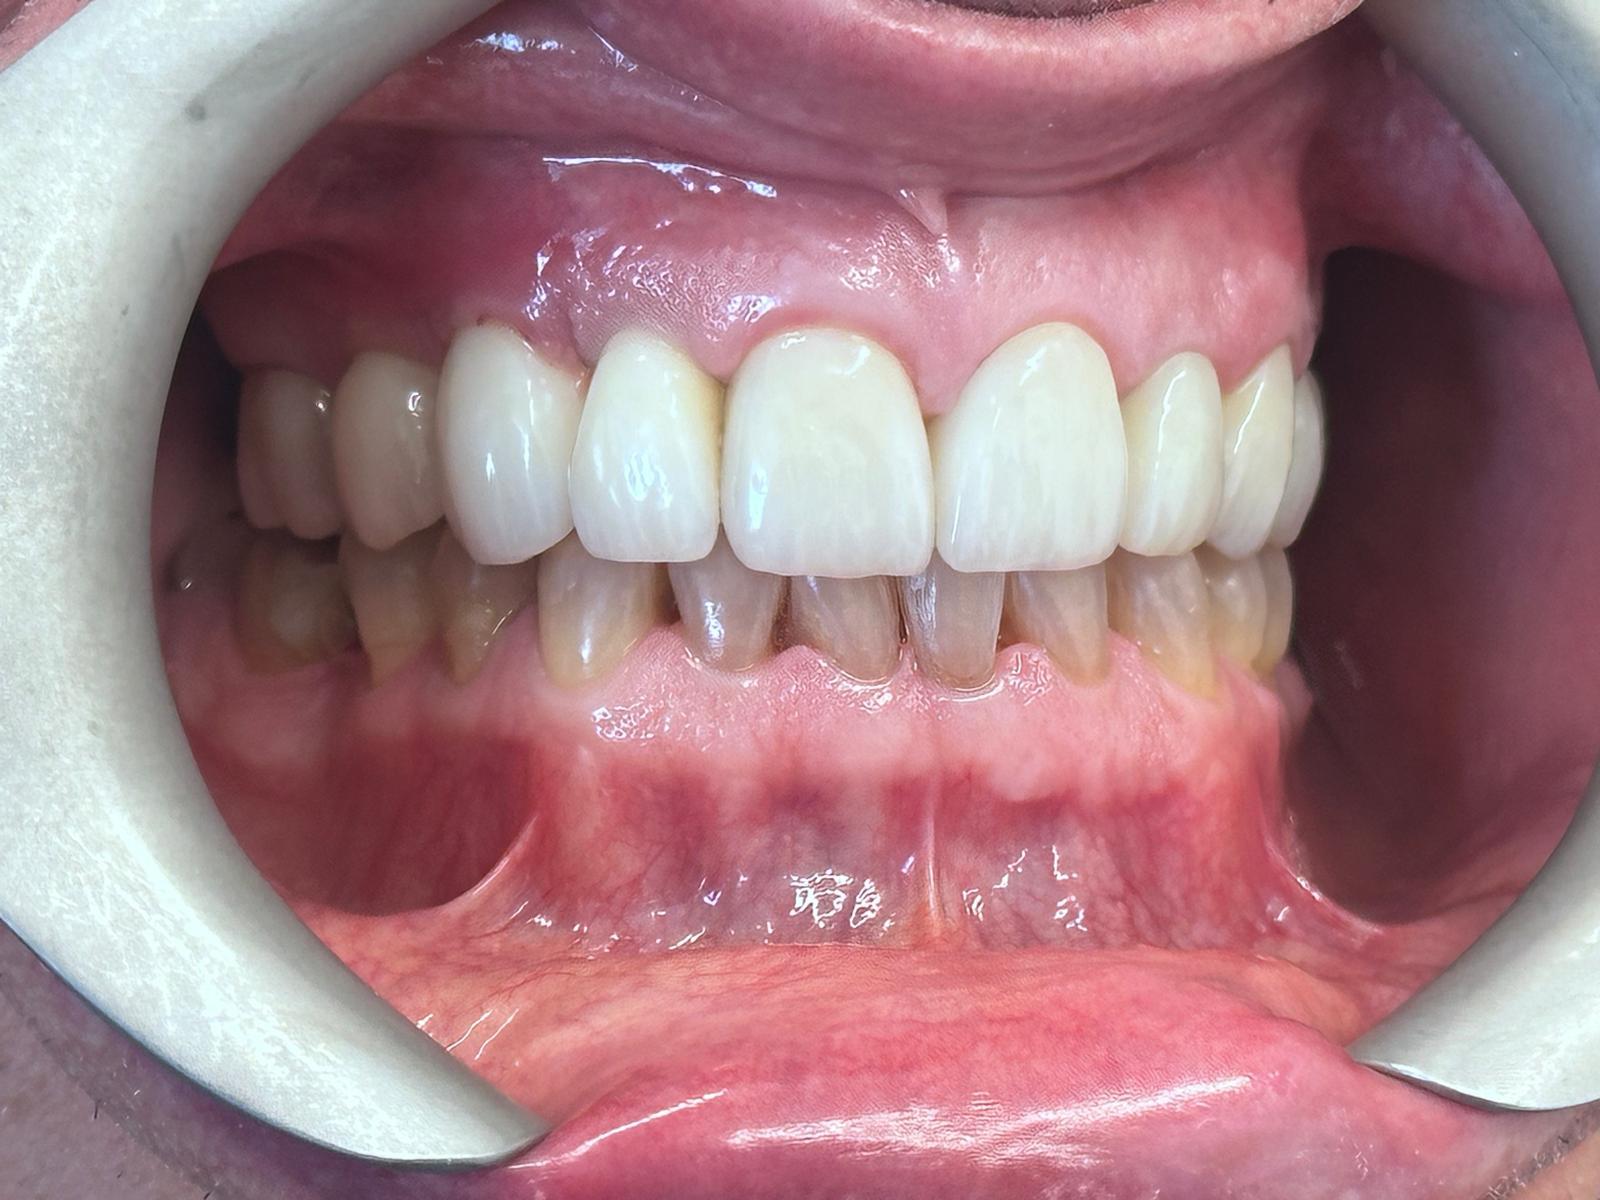

Full smile rehabilitation involving replacement of missing and failing teeth with implant-supported restorations, combined with aesthetic correction of existing dentition. The treatment was carefully planned to restore function, improve alignment, and achieve a balanced, natural-looking smile.

Implants were strategically placed to support long-term stability, with particular attention to soft tissue contours and emergence profiles to ensure seamless integration with the surrounding teeth. The final restoration was designed to enhance both aesthetics and bite function, delivering a confident and harmonious result.

This case demonstrates a comprehensive approach to implant and restorative dentistry, combining surgical precision with advanced prosthetic design to achieve predictable, long-term outcomes.